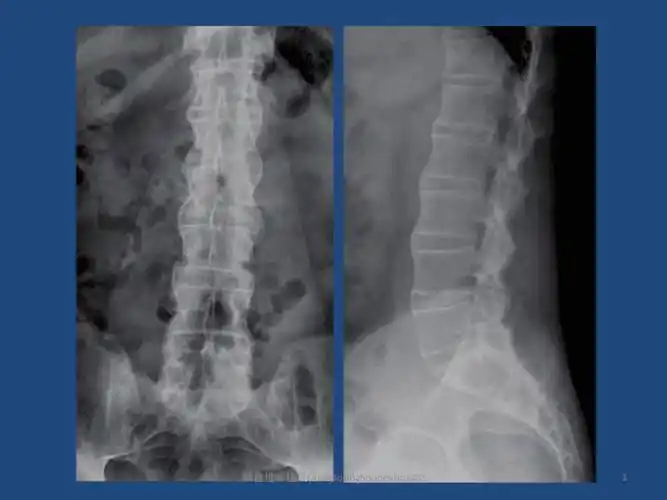

强直性脊柱炎(竹节脊柱)

强直性脊柱炎的影像学表现及训练方法

强直性脊柱炎ankylosingspondylitisas课件